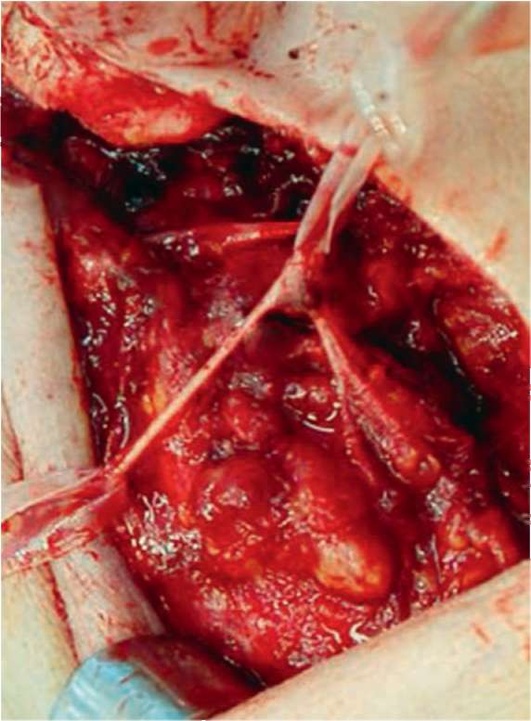

Лечение пациентов слюннокаменной болезнью заключается в удалении конкремента и создании условий, предотвращающих рецидив камнеобразования. Если камень располагается в околоушном или под-нижнечелюстном протоках либо в околоушной железе, то его удаляют. Если камень локализуется в под-нижнечелюстной железе, то его удаляют вместе с железой.

В настоящее время разработаны органосохраняющие операции, при которых в случае расположения камня в поднижнечелюстной железе удаляют конкремент, оставляя слюнную железу (В.В. Афанасьев, М.Р. Абдусаламов).

Удаление камней из поднижнечелюстного и околоушного протоков проводят в амбулаторных условиях. Удаление камней из внутрижелезистых отделов околоушного протока и экстирпацию поднижнечелюстной слюнной железы производят в условиях стационара. Для предупреждения рецидива камнеобразования В.В. Афанасьев рекомендовал проводить операцию по созданию нового устья протока.